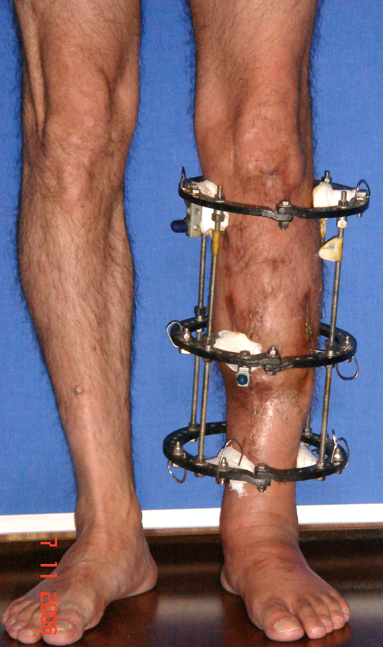

Eksternal fiksatör ile geçen süre (eksternal fiksasyon indeksi), gereken distraksiyon miktarına bağlıdır ve bu süre boyunca bazı komplikasyonlarla karşılaşılabilir. Distraksiyon dönemi sona erdikten sonra, distraksiyon süresinin iki katını aşan konsolidasyon döneminde hastalar eksternal fiksatörü zorlukla tolere edebilirler. Yeterli konsolidasyon sağlanmadan eksternal fiksatör çıkartılırsa ise kırıklar, deformite ve kısalık oluşabilir. Hastanın fiksatör ile birlikte geçirdiği sürenin azaltılması ve böylece hasta konforunun ve aktivite düzeyinin arttırılması için intramedüller çivi üzerinden uzatma yöntemi uygulanmaktadır. Bu yöntemde distraksiyon dönemi sona erdiğinde kemiğin içindeki çivi statik olarak kilitlenmekte ve eksternal fiksatör çıkartılmaktadır. Stabilizasyon intramedüller çivi tarafından sağlandıktan sonra konsolidasyon dönemi gerçekleşmektedir. Bu şekilde hem eksternal fiksatörün uzun süre kalmasından hem de erken çıkartılmasından kaynaklanan komplikasyonların önüne geçilmektedir.